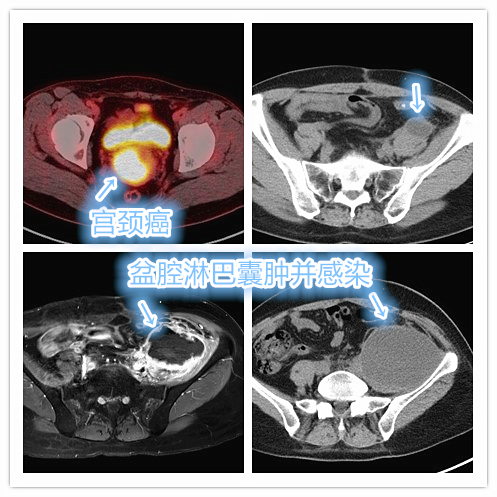

杨女士半年多前因阴道不规则出血,经检查确诊为宫颈癌,所幸发现较为及时,术后病理分期为Ⅰb期,属于宫颈癌早期,术后顺利完成辅助放疗。中晚期宫颈癌治疗后进展怎么办?

但就在2个月前杨女士出现右侧髂腰部酸痛不适,随即复查CT显示盆腔囊性包块,结合病史,考虑为典型盆腔淋巴囊肿。经保守治疗无效后,于当地医院先后行2次经皮穿刺抽液治疗,但单纯抽液后囊腔短期内仍反复。近1周局部肿胀、疼痛感明显加重,并局部皮温升高,考虑盆腔淋巴囊肿并感染。妇科恶性肿瘤术后为何容易出现盆腔淋巴囊肿?

盆腔淋巴囊肿并感染